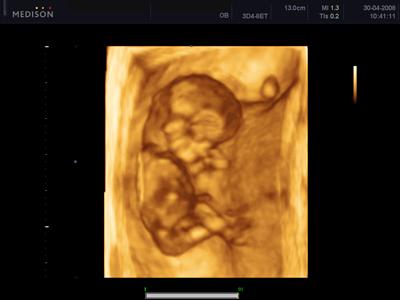

Provozujeme centrum ambulantní gynekologie a porodnictví. Nabízíme komplexní péči o ženu ve všech obdobích života. Provádíme ambulantní hysteroskopii, konizaci, expertní kolposkopii, interupci, abrazi, labioplastiku a 3D i 4D ultrazvuk.